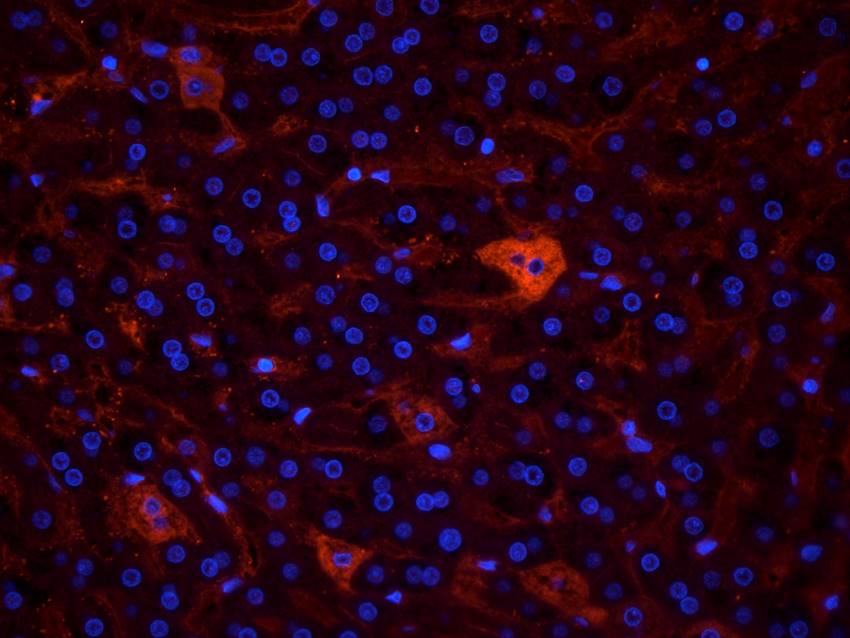

100 μg, 10 μg - Anti-Glucose Transporter GLUT1/SLC2A1 Antibody [orb259612]

FC, ICC, IF, IHC, IHC-Fr, WB

Human, Mouse, Rat

Rabbit

Polyclonal

Unconjugated